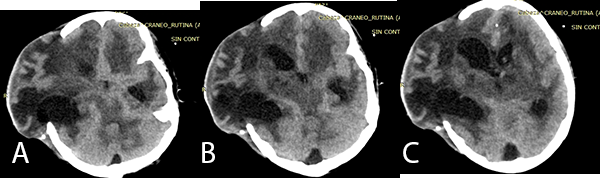

Posterior a la biopsia, el paciente presentó mayor alteración del sensorio, con TEM control evidenciándose hidrocefalia. Se decide la colocación de una Derivación Ventricular Externa (DVE) con medición de la Presión Intra Craneana (PIC) (Imagen 2).

Imagen 2: (A), (B) y (C) TEM cerebral sin contraste en corte axial muestra leve dilatación ventricular con catéter de DVE, además de ligera asimetría entre hemisferios cerebrales.

El paciente no presentó mejoría del estado de conciencia, ingresando a Unidad de Cuidados Intensivos donde se evidencia hipertensión endocraneana refractaria, con mediciones de PIC mayores de 20 mmHg sostenida más de 30 minutos pese a tratamiento neurointensivo. Debido a ligera asimetría interhemisférica (Imagen 2) con hipo densidades sugerentes de edema cerebral frontal derecho es sometido a una Craniectomía Descompresiva.

Imagen 3: (A), (B), (C) TEM cerebral sin contraste cortes axiales previa a la fenestración endoscópica, se evidencia hidrocefalia asimétrica post colocación de DVE en el cuerno frontal izquierdo.

En la TBC del SNC se evidencia que se produce una reacción inflamatoria afectando las cisternas basales con obliteración de las mismas, evidenciándose en la TEM cerebral como exudados isodensos o hiperdensos tal como indica Bathla et al.(10) En la TEM cerebral (Imagen 3) del paciente se evidenció que las cisternas basales se encontraban obliteradas por imágenes ligeramente hiperdensas.